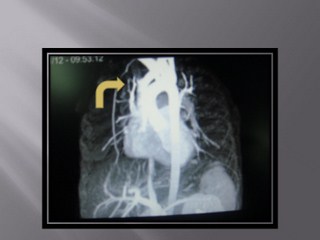

تشخيص :

Vascular Rings